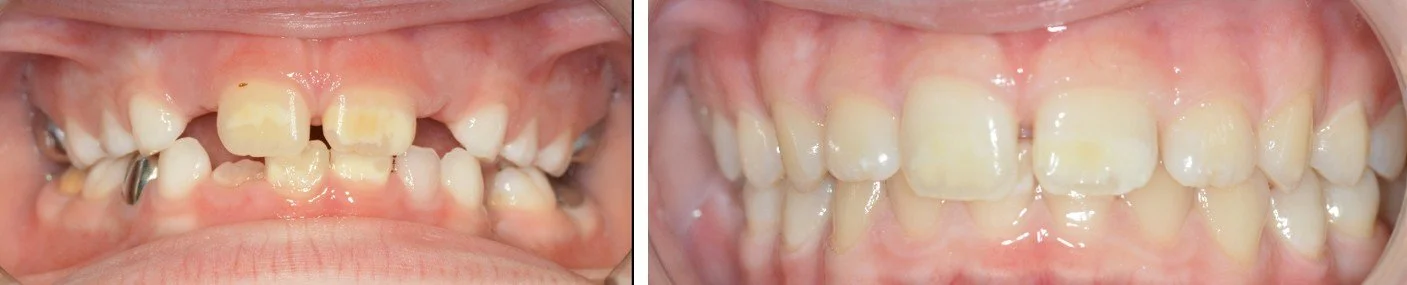

But briefly, we use toothmousse for microabrasion treatments where we seem to get a reasonable outcome in yellow/brown lesions

Management of anterior lesions with a combination technique. We used Toothmousse as part of microabrasion